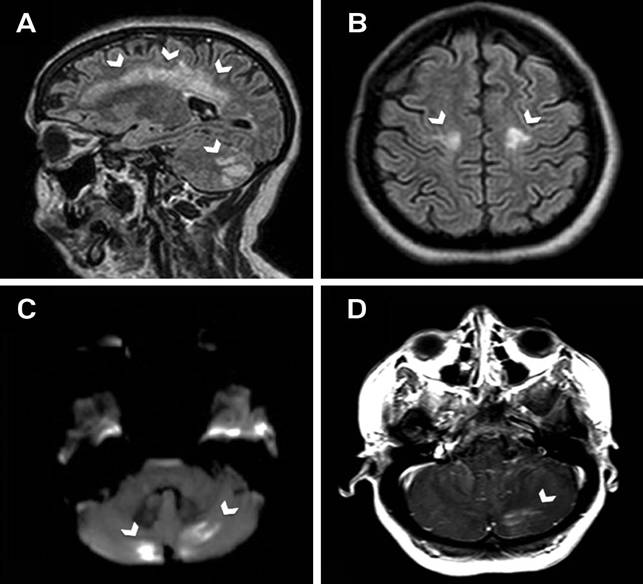

-Trong số các bệnh nhân ở trên, có 4 người cần thiết phải điều trị liều 2 với albendazole, tăng bạch cầu eosin còn lại nghĩ đến các triệu chứng đó là tái phát;

-Một số test huyết thanh chẩn đoán hiện có sẵn trên thị trường để chẩn đoán bệnh giun đầu gai, song nó có rất nhiều thương hiệu và ngưỡng phát hiện dương tính cũng khác nhau tùy thuộc nhà sản xuất pha chế nồng độ có sẵn. Các xét nghiệm ở đây phần lớn thực hiện tại trường đại học Mahidol, Thái Lan và sử dụng Immunoblot để phát hiện band đặc hiệu 24-kDa cho loài Gnathostoma sp., hoặc chẩn đoán dựa trên kit của Bộ môn Ký sinh học, trường Đại học Y dược thành phố Hồ Chí Minh, Việt Nam. Tại các la-bô đó số ca xác định phần lớn nhiễm Gnathostoma, độ nhạy của Immuno blot là 100%, chưa thấy phản ứng dương tính chéo ở kit cho immunoblot và test của Việt Nam chúng ta chưa có số liệu cụ thể về nghiên cứu phản ứng chéo này;.

-Đến nay, thuốc để điều trị đặc hiệu cho loài giun này chưa có, chỉ dùng loại albendazole điều trị như các loại giun tròn khác ở người; may thay, kết quả điều trị hiệu quả lên đến > 90%, tương tự kết quả về hiệu lực thuốc Ivermectin. Trong số đó, 4 bệnh nhân cần thiết phải điều trị liều 2. Các tình huống bệnh như vậy khó xác định được đâu là thất bại điều trị (treatment failure) và đâu là tái nhiễm (reinfection) sau điều trị, dù sao đi nữa sự giảm tỷ lệ bạch cầu eosin và không xuất hiện lại triệu chứng bệnh trong vòng 12 tháng theo dõi cũng được xem là hiệu quả rồi và là chỉ điểm điều trị khỏi đáng tin cậy. Mặc dù phải điều trị lại lần 2 và thuốc Ivermectin cũng như thế, nhưng chúng ta cũng nên đặt ra công tác giám sát tương tác và độc tính thuốc khi dùng liệu trình liều cao và dài ngày;

H13

Một chẩn đoán hướng đến bệnh ký sinh trùng giun đầu gai G. spinigerum nên được đặt ra cho bệnh nhân khi có bệnh sử với triệu chứng sưng phồng, ban trườn, ấu trùng di chuyển dưới da, triệu chứng tiêu hóa không đặc hiệu xuất hiện thoáng qua, kèm với yếu tố dịch tễ của bệnh nhân.

Quản lý bệnh thường đưa ra lời khuyên hợp lý về chế độ và vệ sinh an toàn thực phẩm. Ý thức và chế độ ăn uống của bệnh nhân hợp lý hay chưa vì hiện nay xu hướng ăn uống các trung gian truyền bệnh của các tác nhân ký sinh trùng này tương đối phổ biến trong cộng đồng dân, kể cả tại Việt Nam.